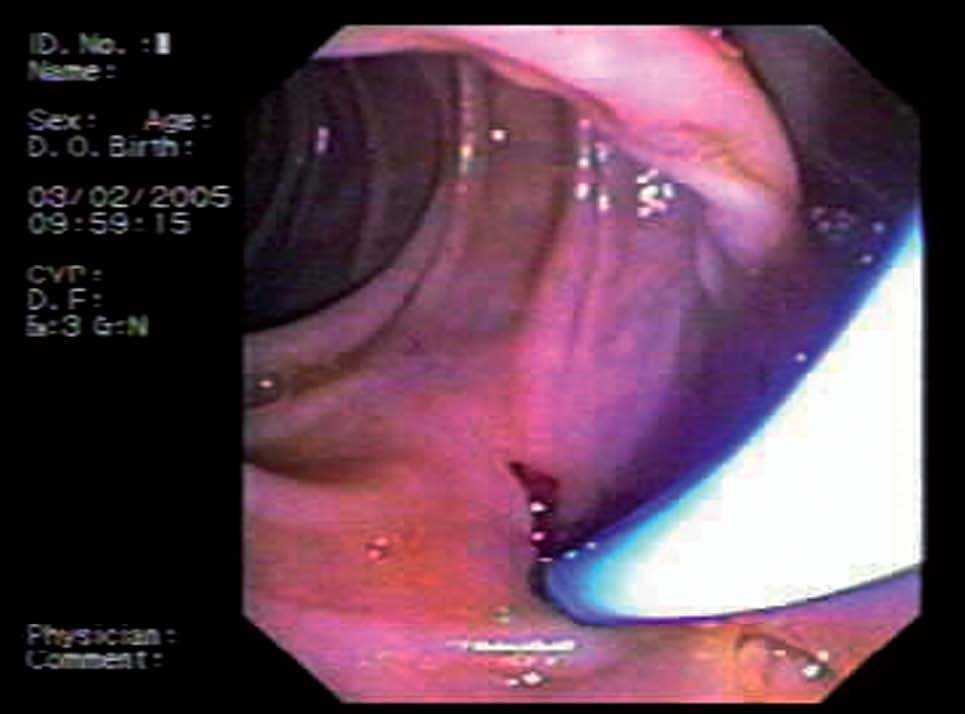

Mujer de 76 años de edad, con antecedentes personales de colecistectomía 30 años antes y de esfinterotomía endoscópica hace 10, por coledocolitiasis. Ingresa en nuestro servicio por presentar colestasis. Los datos analíticos más relevantes son: bilirrubina total 3 mg/dl (0-1,1), GGTP 892 U/l (8-61), fosfatasa alcalina 530 U/l (40-129), GOT 94 U/l (6-38) y GPT 62 U/l (6-41). Se realizan ecografía abdominal y colangio-RM que ponen de manifiesto la presencia de dilatación de las vías biliares y estenosis de la coledocoduodenostomía previa. Ante estos hallazgos, se coloca una prótesis biliar y se realiza drenaje interno-externo. Esta técnica se lleva a cabo en colaboración con el radiólogo intervencionista. En primer lugar, por vía transparietal-hepática se introduce una guía metálica hasta la ampolla de Vater. El endoscopista por vía duodenal sitúa una prótesis de plástico de 10 F y 7 cm, comprobando al terminar el buen anclaje de la misma (fig. 1). Tres días después del procedimiento la paciente refiere dolor abdominal y naúseas, por lo que se solicita nueva ecografía abdominal que demuestra que la prótesis está en el conducto hepático izquierdo. El intento de extracción mediante CPRE resulta infructuoso, por lo que finalmente la prótesis se recupera por vía transparietal-hepática (fig. 2).

Fig. 2. Extracción de prótesis migrada a conducto hepático izquierdo.